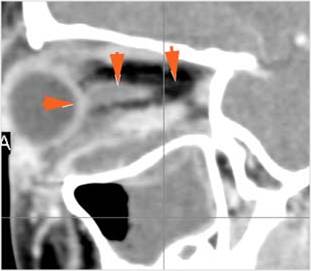

Nasal Cavity and Nasolacrimal Drainage System

There is mucoperiosteal thickening in the nasal cavity. [Yes/No]

There is ulceration or erosion of the nasal septum or turbinates. [Yes/No]

There is mucosal thickening of the posterior lateral walls of the nasal cavity, cribriform plate or the face of the sphenoid bone. [Yes/No]

There is infiltration of the fat surrounding the nasolacrimal sac. [Yes/No]

There is infiltration of soft tissues or bone erosion along the nasolacrimal fossa or canal. [Yes/No]

Sinuses

There is soft tissue swelling anterior to the frontal sinus or in the soft tissues surrounding the maxillary sinuses. [Yes/No]

There is mucoperiosteal thickening in the sinuses. [Yes/No]

There is mucosal enhancement in the sinuses. [Yes/No]

There is an air fluid level in the frontal sinus. [Yes/No]

There is bone erosion along the walls of any affected sinuses. [Yes/No]

There is an appearance of bone expansion, due to regressive remodeling and suggestive of pre-existing mucocele, along the walls of any affected sinuses. [Yes/No]